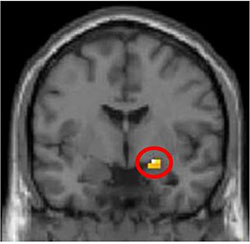

This is an MR-image of amygdala activity while playing the Ultimate Game. (Credit - The article authors (Gospic et al) and PLoS Biology.)

In the present study, the subjects were either given the anti-anxiety tranquilliser Oxazepam or a sugar pill (placebo) while playing the Ultimate Game. The researchers found that those who had received the drug showed lower amygdala activity and a stronger tendency to accept an unfair distribution of the money – this despite the fact that when asked, they still considered the suggestion unfair.

In the control group, the tendency to react aggressively and punish the player who had suggested the unfair distribution of money was directly linked to an increase in activity in the amygdala. A gender difference was also observed with men responding more aggressively to unfair suggestions than women and showing a correspondingly higher rate of amygdalic activity. This gender difference was not found in the group that received Oxazepam.